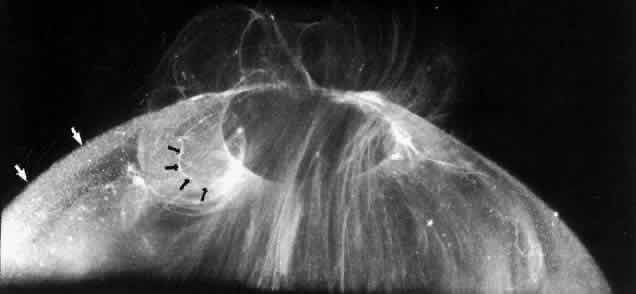

Researchers88–91have used these techniques to study human vitreous structure. Within the adult human vitreous there are fine, parallel fibers coursing in an anteroposterior direction, as shown in Figs. 4B AND C, 5, and 6. The fibers attach into the vitreous base (see Figs. 4H and 5) where they splay out anterior and posterior to the ora serrata. As the peripheral fibers course posteriorly they are circumferential with the vitreous cortex, while central fibers “undulate” in a configuration parallel with Cloquet's canal.6 The fibers are continuous and do not branch. Posteriorly, these fibers attach into the vitreous cortex (see Fig. 4E and F), but not the internal limiting lamina of the retina.

Fig. 5. Posterior and central vitreous of a 59-year-old man. Fibers course anteroposteriorly in the center of the corpus vitreous and enter the retrocortical space through the premacular region of the vitreous cortex (to the top at the center). Within the cortex are many small “dots” that scatter light intensely (white arrows). The larger, irregular dots are debris. The smaller dots are hyalocytes. (Sebag J: The Vitreous--Structure, Function and Pathobiology. New York, Springer-Verlag, 1989)

Fig. 6. Vitreous structure in a 58-year-old woman. Fibers course anteroposteriorly in the central and peripheral vitreous. Posteriorly, fibers orient to the premacular region (top). Anteriorly, the fibers “splay out” to insert into the vitreous base (bottom right). (Sebag J: The Vitreous--Structure, Function and Pathobiology. New York, Springer-Verlag, 1989)